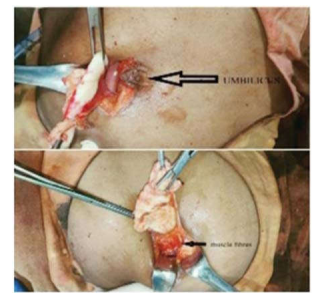

: The abdominal cyst adhered to the fibers of the uterus and urinary bladder

Calcified hydatid cyst en-mass after Pericystectomy

Description: No description available.

Intra-operative port site hydatid cyst.